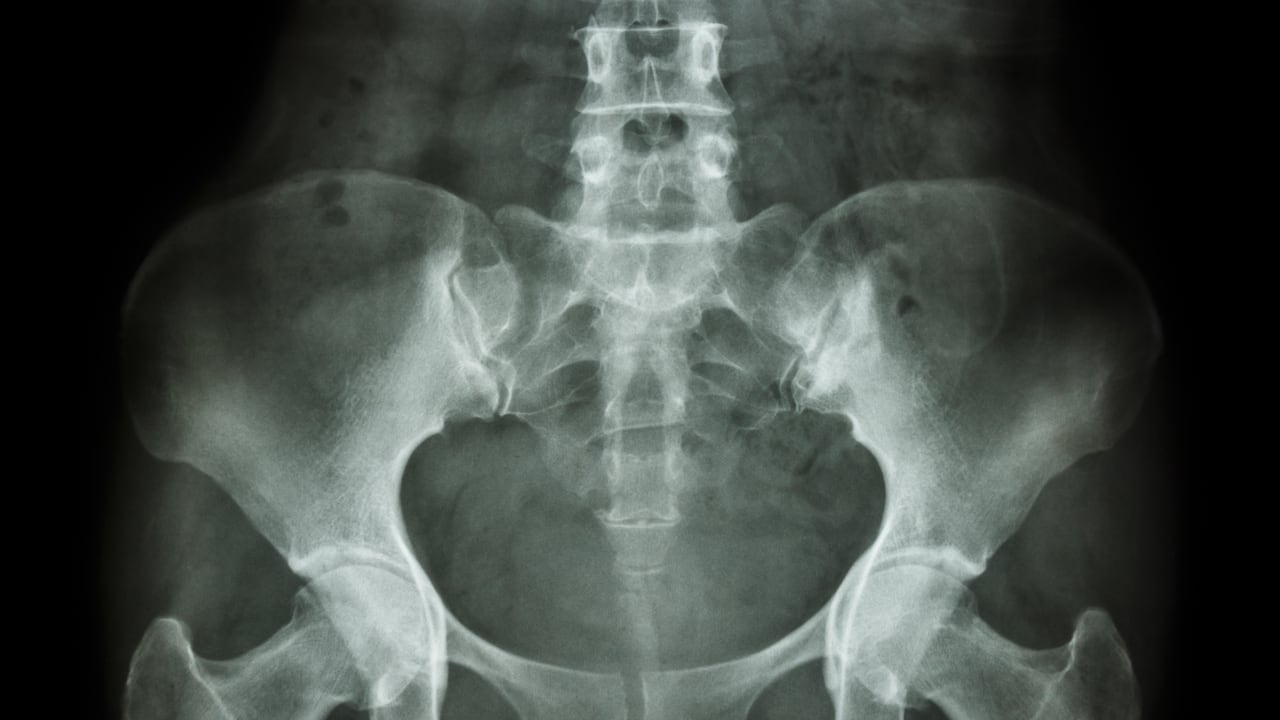

La densidad ósea se refiere a la cantidad de masa ósea presente en una determinada área de los huesos. En otras palabras, es una medida de cuánto tejido óseo hay en relación con el volumen del hueso. Esta propiedad es un indicador crucial de la salud ósea y se relaciona directamente con la fortaleza y la resistencia de estas estructuras necesarias para el buen funcionamiento del organismo.

Una mayor densidad ósea significa que los huesos son más fuertes y menos propensos a fracturarse o romperse. Los huesos fuertes son esenciales para mantener la movilidad, la independencia y una buena calidad de vida a medida que se envejece.

De igual manera, una densidad ósea adecuada puede ayudar a prevenir enfermedades como la osteoporosis, una condición caracterizada por la disminución de esta propiedad y un mayor riesgo de fracturas.

De acuerdo con un artículo académico publicado en Científica, una revista especializada de la Escuela de Nutrición y Dietética de la Universidad Científica del Sur, en Perú, “el consumo de cafeína reduce la densidad mineral ósea, incrementa el riesgo de sufrir fracturas en la cadera e influye negativamente en la retención de calcio”.

Sobre esta conclusión el documento refiere un estudio realizado en Suecia que concluyó que mujeres posmenopáusicas que consumen 330 miligramos de cafeína al día, unas cuatro tazas, son más propensas al riesgo de fracturas osteoporóticas, especialmente si el consumo de calcio es inferior a los 700 miligramos cada día, que aquellas que solo toman una sola taza de café.